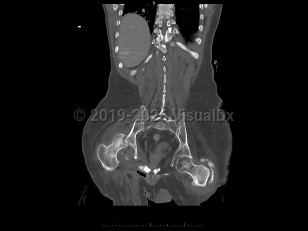

Traumatic hip dislocation

Hip fracture

Avascular necrosis of hip

Femoral neck fracture

Femoral neck stress fracture